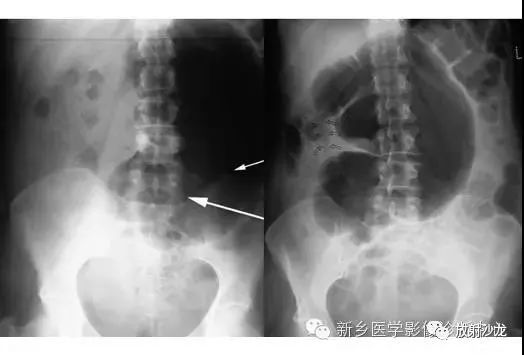

上图符合53岁,女性,肠梗阻所做的腹部平片。发病初所拍图像在左侧,24小时后所拍图像在右侧。是什么原因造成病人梗阻?众多发现都在眼前,不要被箭头影响。

该患者存在一个大的盲肠肠扭转。左侧图像显示一个没有任何可见结肠袋(短箭头),内脏充满大量气体。在升结肠(红色箭头)存在粪便与空气,这表明没有完全阻塞并且一些气体正向远端移动。右图像显示内脏位置的变化,这表明梗阻是非固定的。扭转是由弯曲的箭头所圈出。典型的表现为盲肠头朝向右侧髂窝与肠扭转突出向上朝向左上腹部。